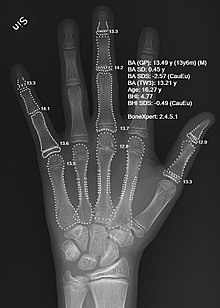

Determination of bone age allows for comparison with chronological age and assessment of future growth potential.

Since bone maturation is a good indicator of overall physical maturation, an x-ray of the left hand and wrist to assess bone age usually reveals whether the child has reached a stage of physical maturation at which puberty should be occurring.[3][7] X-ray displaying a bone age <11 years in girls or <13 years in boys (despite a higher chronological age) is most often consistent with constitutional delay of puberty.[7][40] An MRI of the brain should be considered if neurological symptoms are present in addition to delayed puberty, two findings suspicious for pituitary or hypothalamic tumors.[3][10] An MRI can also confirm the diagnosis of Kallmann syndrome due to the absence or abnormal development of the olfactory tract.[10] However in the absence of clear neurological symptoms, an MRI may not be the most cost-effective option.[10] A pelvic ultrasound can detect anatomical abnormalities including undescended testes and müllerian agenesis.[3][39]